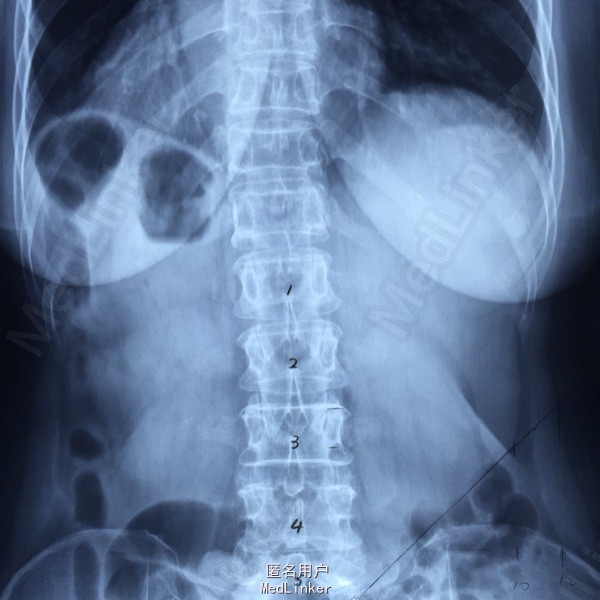

65岁女性,右下肢放射性疼痛2年半,保守治疗效果不佳 2年前曾行C5-6的ACDF术。

L5-S1左侧棘旁压痛(+),右小腿外侧针刺觉稍弱,右侧跟腱反射稍弱。 腰椎CT提示L5-S1间盘突出,偏右侧。 腰椎X线片提示髂嵴偏高,L5横突肥大。

L5-S1椎间盘突出 C5-6 ACDF术后 拟行椎间孔镜手术